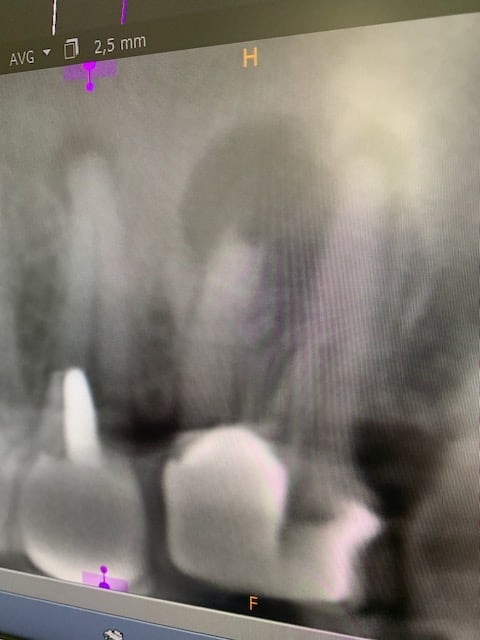

Beaucoup de blabla et toujours pas de radio.

C’est important parce que si c’est toi qui a fait ça, ou équivalent, (cas ci dessous), c’est indéfendable.

Ça cause des douleurs parfaitement compréhensibles, douleurs dont tu te gardes bien de reparler dans ton roman.

Douleurs qui sont à l’origine de tes problèmes.

Il t’a été posé la question de savoir si la patiente n’était pas venu te consulter pour ces douleurs avant d’aller voir ailleurs.

Encore une question qui dérange à laquelle tu n’as répondu… comme c’est bizarre …

Ça sent l’embrouille ton histoire sans images.